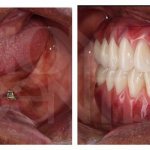

Насколько оттенков получится осветлить?

Эффект отбеливания невозможно определить заранее с точностью. Любой человек индивидуален и результат от Вайт Смайл у каждого проявляется по-своему.

Стоит отметить! В зависимости от желаемого эффекта можно выделить 3 вида отбеливания:

- Экспресс (2-4 тона, 20 минут);

- Классик (4-8 тонов, 40 минут);

- Экстра (8-12 тонов, 60 минут).

Для максимального результата рекомендуется выбирать сеанс Экстра или Классик. Для повторного сеанса и поддержания результата советуют Экспресс.

Каждый человек сам для себя определяет, на какое количество тонов необходимо отбеливание.